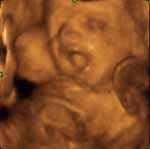

o Código Penal incluirá mais uma situação em que o aborto não é punível: «por opção da mulher, nas primeiras 10 semanas de gravidez»;

- “As ecografias não mostram o bebé, mostram outra coisa qualquer”, frase proferida por uma apoiante do Sim na estação de Metro da Trindade